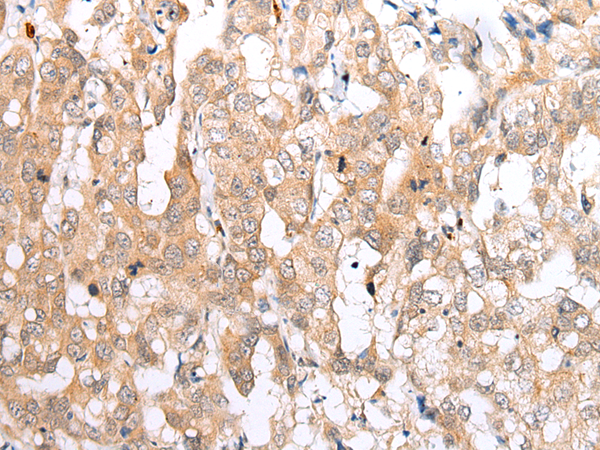

IHC positive control: |

Human prostate cancer and human breast cancer |